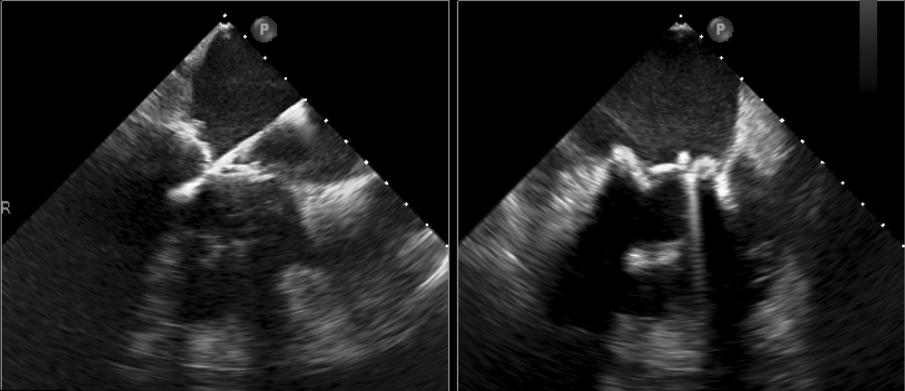

术中影像监护与评估(DSA&TEE)

原生物瓣少量反流

过瓣流增快,呈“五彩状”

CDFI提示过瓣血流通畅

CDFI示少量瓣周漏

收缩期未见瓣周漏